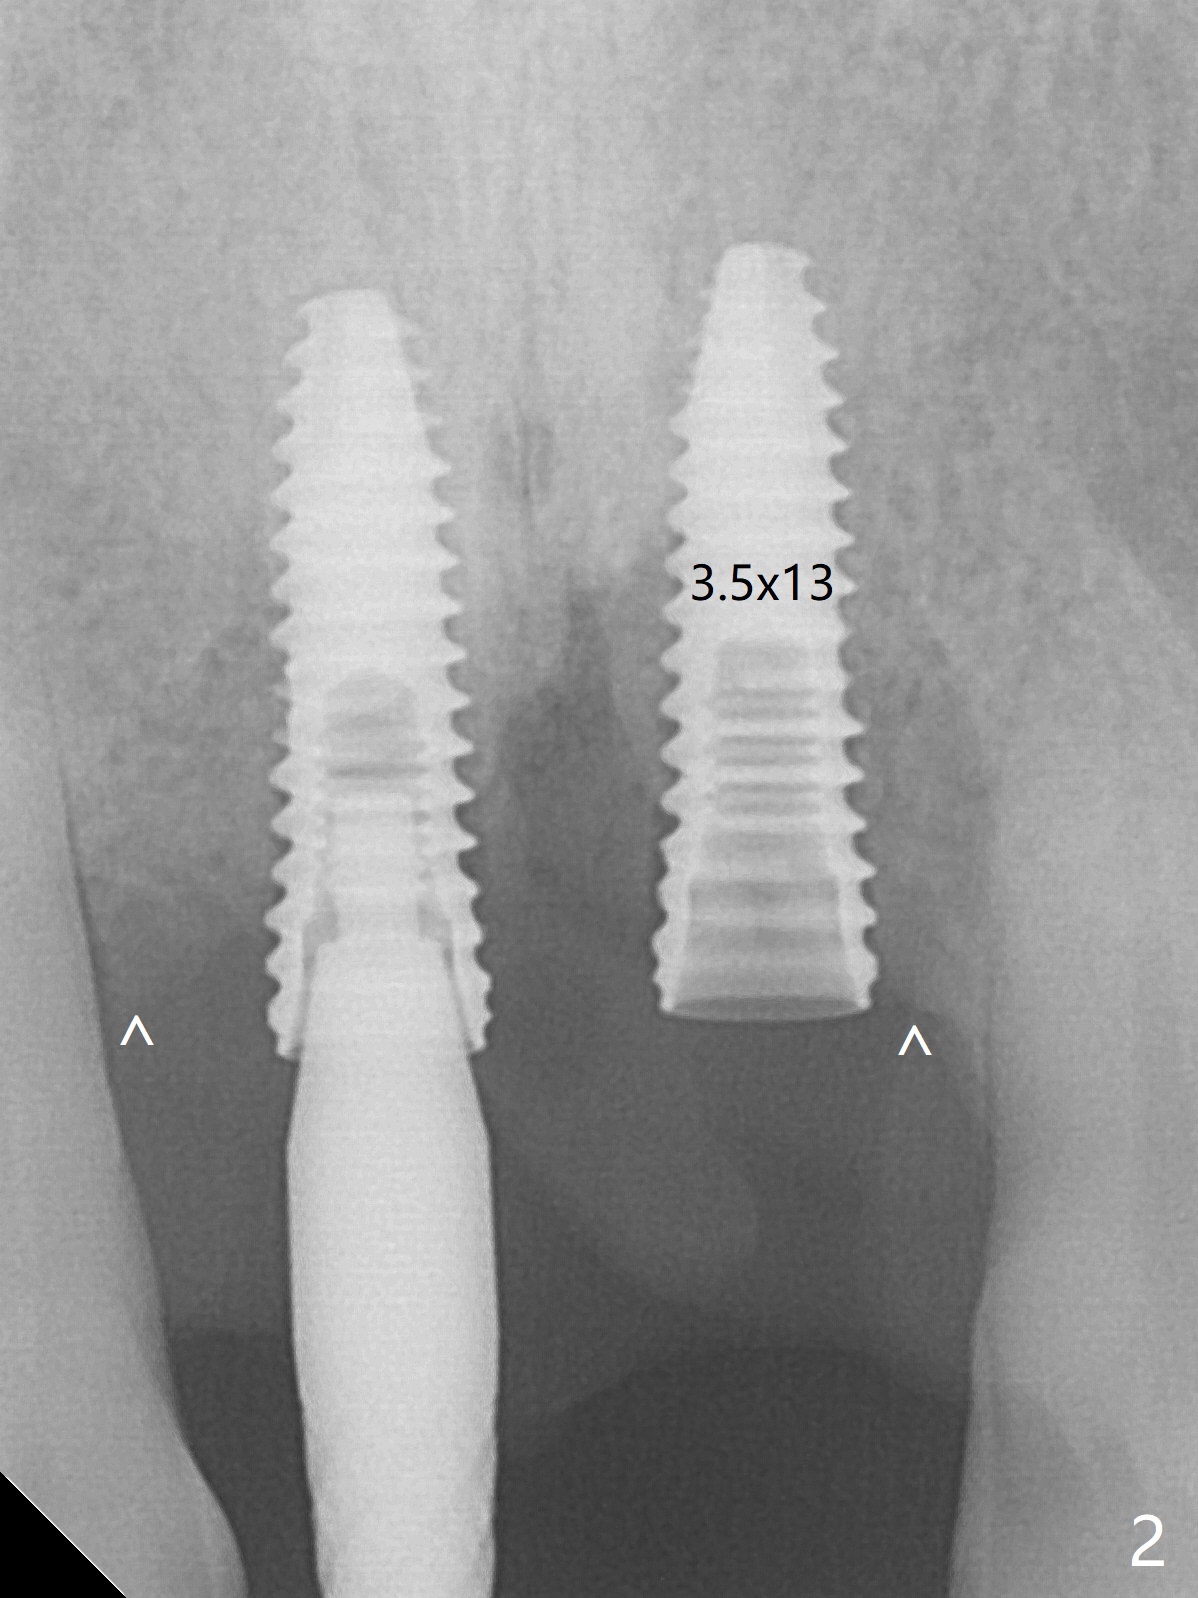

There is no buccal plate at #8 or 9 when the teeth are extracted as well as severe soft tissue defect at #8. Osteotomy is initiated as palatal as possible (Fig.1). When 3.5x13 mm implants are placed initially, the one at #8 is supracrestal (Fig.2 ^). To reduce the chance of peri-implantitis, the implant is placed deeper (Fig.3 (~2 mm implant threads exposed buccally)) with placement of sticky bone around the implants and 4.5x5.5(4) mm abutments (Fig.3 *). The buccal soft tissue defect #8 is repaired with a piece of PRF membrane (Fig.4 *), followed by periodontal dressing. Smaller 2-piece implants (3 mm, IBS) with smaller abutments (4 mm) may further reduce chance of periimplantitis and easy buccopalatal reduction of the abutments for restoration. The periodontal dressing remains stable 7 days postop (Fig.5) because it wraps around the abutments (Fig.6 A). By the time the periodontal dressing gets loose, #8 buccal soft tissue defect should be healing. When breaking-down periodontal dressing is removed 17 days postop, the coronal abutments and bone graft are exposed; after fabrication of provisional crowns (Fig.7), periodontal dressing is re-applied buccally. When the second dressing dislodges 5 weeks postop, the buccal soft tissue appears to reduce (Fig.8). Raising flaps may be less traumatic. A piece of bone graft is being extruded 4 months postop (Fig.9 >). After the abutments change from 4.5x5.5(4) to 4.5x7(3) mm, new temporary crowns are fabricated (Fig.10 (4.5 months postop)). CT shows apparent buccal bone at #8 and 9 (Fig.11,12). How to improve cosmetic?